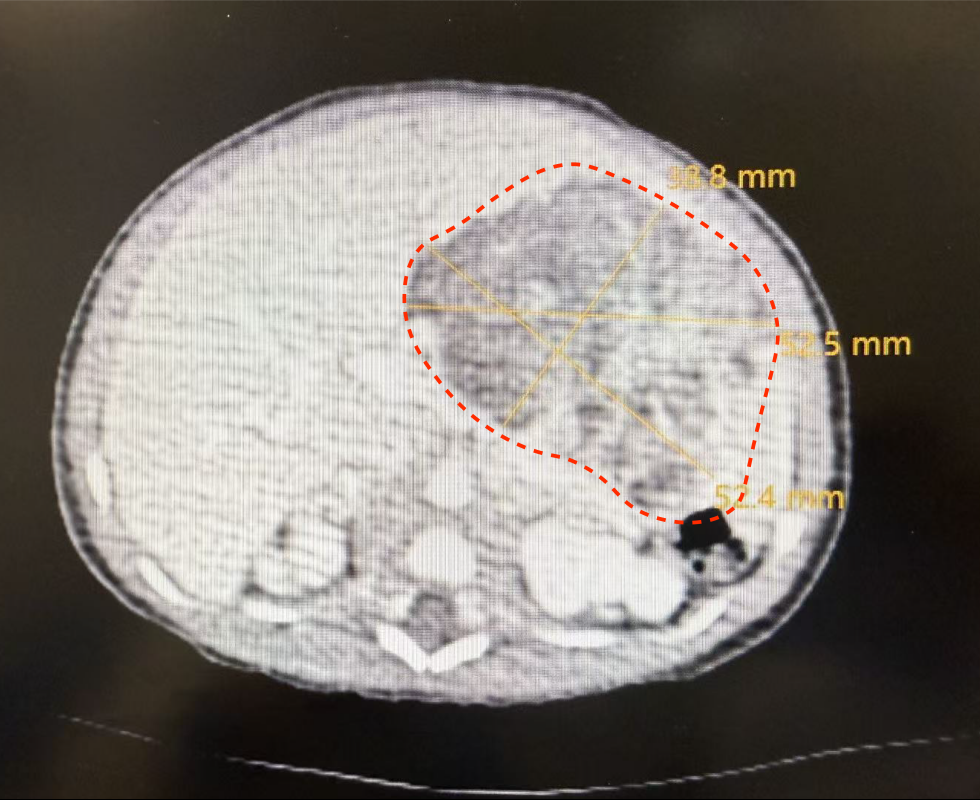

手术的成功,始于术前一次至关重要的“精准侦察”——针对新生儿的多学科协作增强CT检查,这远非一次普通的拍片。“新生儿的增强CT检查,本身就是一次高难度的多学科配合演练。”医学影像科副主任郭建新介绍。由于患儿肿瘤血供复杂,位置紧邻重要血管与脏器,必须通过静脉注射造影剂进行增强扫描,才能获得清晰的“作战地图”。然而,新生儿血管细如发丝、循环系统脆弱,造影剂的剂量、流速必须极度精确,且检查过程中患儿必须绝对安静,任何移动都会导致图像失效。这就需要一个精密配合的“铁三角”:儿童外科医生提出对影像的具体需求;医学影像科团队量身定制低辐射剂量、快速扫描方案,并精确计算造影剂用量;在麻醉科团队协作下,最终生成了清晰的显示肿瘤与周围组织结构关系的CT图像,为手术精准并完整切除肿瘤病灶提供了可靠依据。

有了影像与麻醉基础,陆港院区儿童外科刘仕琪团队开始了肿瘤精准切除。凭借术前影像的清晰引导,团队迅速明确肿瘤源于胃壁。在手术团队精确操作下,历时2小时40分钟,肿瘤被完整切除,术中有效保护好相邻重要器官与组织。术后,患儿转入新生儿科监护室,目前已顺利脱离呼吸机,开始经口喂养,即将转入普通病房。